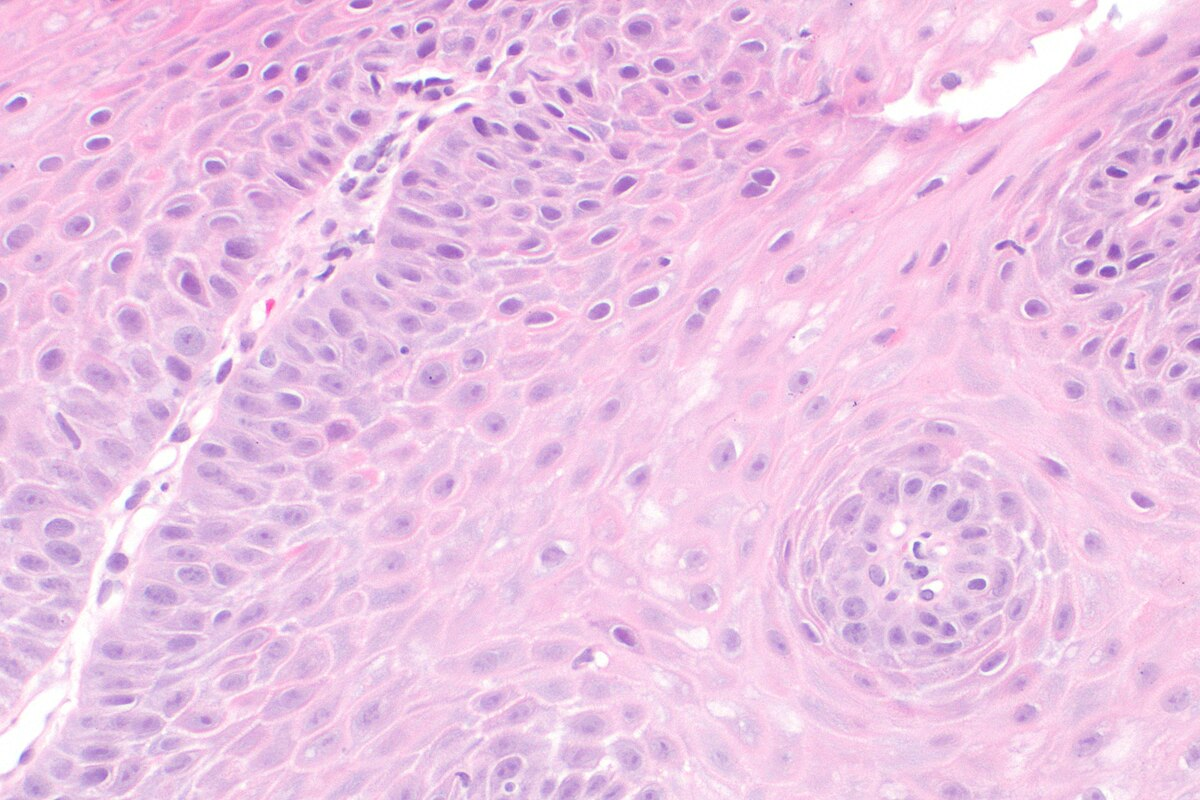

Structural Changes: Airway Remodeling in Asthma

In asthma, the airways change a lot, known as airway remodeling. These changes make it hard to breathe and make the disease worse.

Epithelial Changes

The airway’s first defense is the epithelium. In asthma, this layer gets damaged. There’s more goblet cells and less mucociliary clearance.

This means more mucus and trouble clearing it. It blocks the airways.

Subepithelial Fibrosis

Subepithelial fibrosis is a big part of asthma. It’s when collagen and other proteins build up under the epithelium. This makes the airway wall thicker.

It makes breathing harder and airways more sensitive.

Smooth Muscle Hypertrophy and Hyperplasia

Asthma also makes airway smooth muscle cells bigger and more. This makes it harder to breathe. It’s because of too much muscle.

It’s caused by inflammation and growth factors working together.

Key features of airway remodeling include:

- Epithelial damage and goblet cell hyperplasia

- Subepithelial fibrosis and thickening of the airway wall

- Smooth muscle hypertrophy and hyperplasia

- Increased mucus production and impaired mucociliary clearance

Understanding these changes is key to treating asthma. By focusing on remodeling, we can lessen the disease’s impact. This improves life for asthma patients.